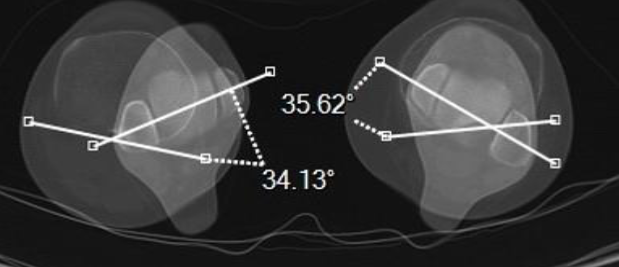

TA-GT

C + E (condyles + TTA)

E

TTA

C

Condyles (Arche romaine)